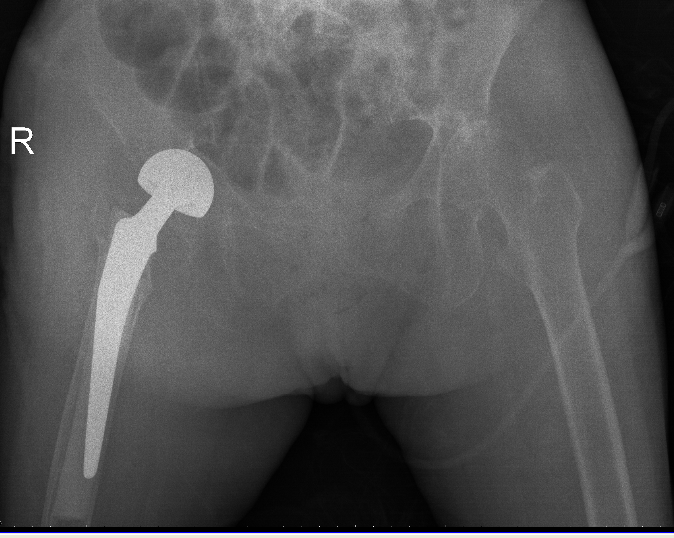

△右側(R)是賴婆婆3年前跌斷股骨術後,左側是本次手術術後。